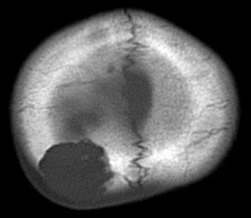

生検術だけして経過を見ると骨欠損が修復される

中年の女性の頭頂部に発生したものです。症状は頭皮の膨隆でした。生検術でLCHと診断して,しばらく経過を見たら自然退縮しました。

左は発症時,右は2年後のCTです。骨欠損部は自然修復されています。LCHの小さな骨欠損は頭蓋形成しなくても良いです。